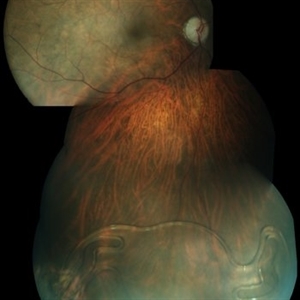

FEVR

Fundus photograph of a 8-year-old female with C/O DM/VN OS showing vitreous traction band dragging of macular and disc OD showed retinal detachment

Photographer: ADITYA JYOT EYE HOSPITAL,MUMBAI INDIA

Condition/keywords: familial exudative vitreoretinopathy (FEVR)